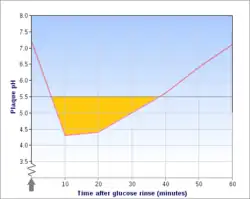

Exposure

The frequency with which teeth are exposed to cariogenic (acidic) environments affects the likelihood of caries development. After meals or snacks, the bacteria in the mouth metabolize sugar, resulting in an acidic by-product that decreases pH. As time progresses, the pH returns to normal due to the buffering capacity of saliva and the dissolved mineral content of tooth surfaces. During every exposure to the acidic environment, portions of the inorganic mineral content at the surface of teeth dissolve and can remain dissolved for two hours.[33] Since teeth are vulnerable during these acidic periods, the development of dental caries relies heavily on the frequency of acid exposure.

The carious process can begin within days of a tooth's erupting into the mouth if the diet is sufficiently rich in suitable carbohydrates. Evidence suggests that the introduction of fluoride treatments has slowed the process.[34] Proximal caries take an average of four years to pass through enamel in permanent teeth. Because the cementum enveloping the root surface is not nearly as durable as the enamel encasing the crown, root caries tend to progress much more rapidly than decay on other surfaces. The progression and loss of mineralization on the root surface is 2.5 times faster than caries in enamel. In very severe cases where oral hygiene is very poor and where the diet is very rich in fermentable carbohydrates, caries may cause cavities within months of tooth eruption. This can occur, for example, when children continuously drink sugary drinks from baby bottles (see later discussion).